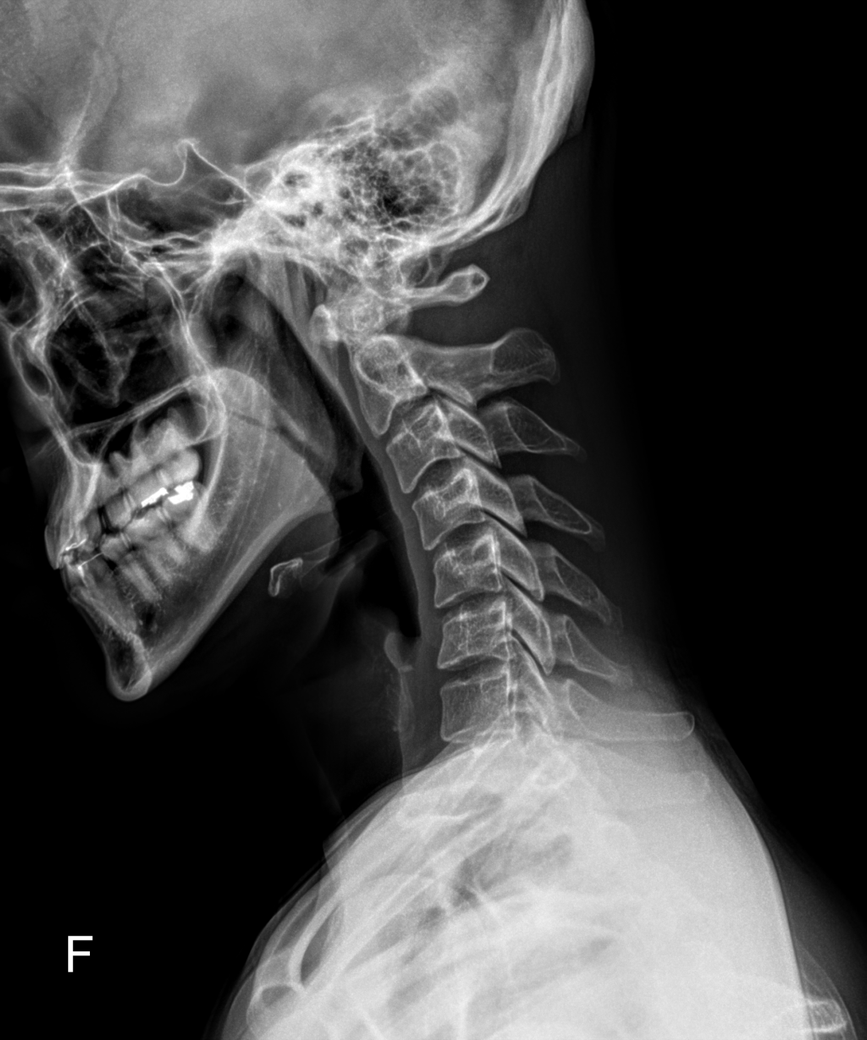

목 xray찍어봤는데 거북목 많이 심한건가요? 부탁드립니다..

무거운 옷을 입고 자주 나갔더니 어깨 통증이 있어서 근처 정형외과에서 x-ray를 찍어봤는데요

아래 사진처럼 나왔습니다.

의사선생님께서는 거북목이 엄청 심하다고, 나이가 있어서 완벽한 교정에 회의적이라 하셨구요

물리치료사분께서는 근래 본 거북목 환자 중에 가장 심하다면서 주 3회 도수 치료 받자고 하셨어요...

거북목인건 알았는데 그렇게 심한건가요...?

목 뼈는 정상적으로 C자 모양을 보여야하는데, 질문자 님은 목뼈가 일자 또는 약한 역 C자 형태로 심한 거북목에 해당합니다.